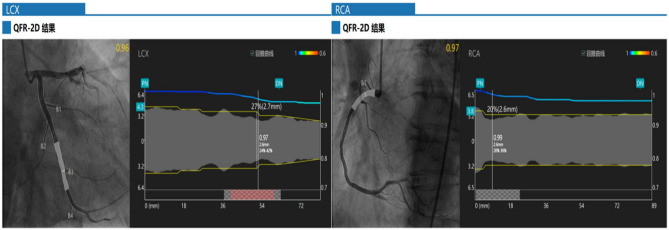

Methods: This single-center ambispective cohort study retrospectively screened patients with CHD and T2DM who underwent two coronary angiographies from March 2021 to December 2023. Propensity score matching was used to equilibrate baseline factors between two groups: with 106 patients receiving dapagliflozin therapy (experimental group) and 106 patients not receiving dapagliflozin (control group). The retrospective part assessed the effect of SGLT2i on coronary microcirculatory function in patients with CHD and T2DM using the change in Angiography-derived Coronary Microcirculatory Resistance (AMR) from baseline to 12±1 months after treatment as the primary endpoint. The prospective portion of the study followed patients for 15 months to assess clinical outcomes. The study was registered with the China Clinical Trial Registry (ChiCTR2400085512).